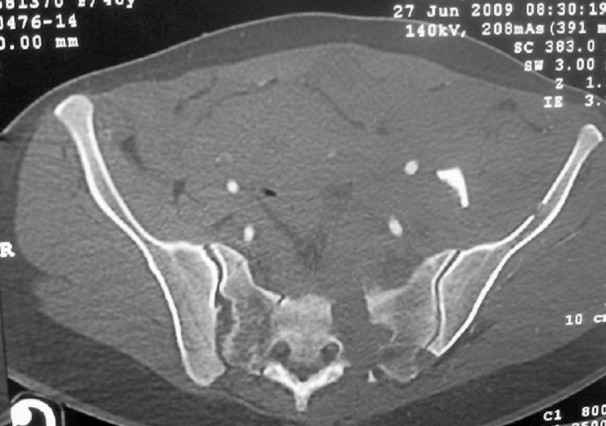

I'm posting this case on behalf of Dr. Pedro Caba, he is unable to post but able to read. 41 yo female , fall from 10 meters five days ago. Hemodynamically unstable on admission treated by angio and embolization and skeletal traction, with no external support. No associated injuries. Based on CT scan the pt has a both column fracture with conminuted dome and displaced anterior column and a sacral Denis 1 fracture with a displaced left ala. I think the best approach for the acetabular fracture is ilioinguinal with Smith-Petersen extension but don't know exactly the sequence . Will you start with the sacral fracture? Which technique? Thanks in advance Pedro Caba Unidad de Trauma Hospital 12 de Octubre Madrid Spain

This patient has extensive and complicated skeletal injuries...much more data (such as additional relevant images and clinical information regarding the soft tissues and overall patient status) would help us formulate an informed plan.

The sacral pattern alone is quite difficult and seems to be some version of an H-pattern, but I can’t tell from these films.